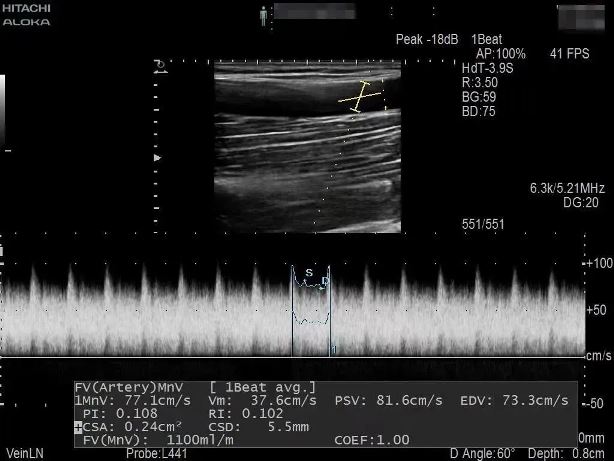

為了節(jié)約患者有限的血管資源,盡早治療,經過腎病內科金明花主任及科室共同討論并爭得患者家屬同意后,決定對患者進行超聲引導下動靜脈內瘺球囊擴張術+血栓碎栓術解決內瘺狹窄及血栓。手術過程中金明花主任在內瘺狹窄位置近心端進行穿刺,沿穿刺針置入導絲、置入血管鞘,在超聲實時引導下球囊到達病變部位,緩慢擴張球囊,解決狹窄病變,并壓碎血栓,使內瘺通暢。整個手術僅用30分鐘,用時少,效果明顯,術后內瘺血管雜音及震顫明顯,手術效果立竿見影。